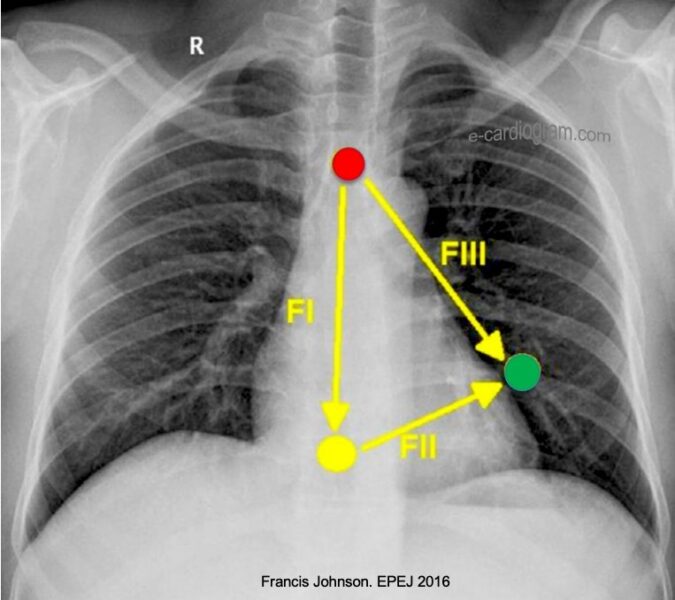

Pour obtenir les dérivations de Fontaine (notées FI, FII, FIII) qui vont s’inscrire à la place de V1V2V3, on déplace les électrodes des membres sur le thorax :

- Rouge (RA) : Sur le manubrium sternal.

- Jaune (LA) : Sur le processus xiphoïde.

- Noir (RL) : Position standard (électrode neutre).

- Vert (LL) : Au 5ème espace intercostal droit (ligne médio-claviculaire) en lieu et place de V4.